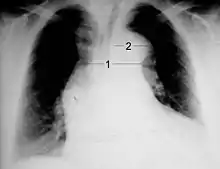

Radiografía de tórax

En un estudio la radiografía de tórax tuvo una sensibilidad moderada (del 67%) en la detección de una disección aórtica evidente.[10]

El 'calcio signo' es un hallazgo en la radiografía de tórax que sugiere disección aórtica. Es la separación de la íntima de la calcificación de tejidos blandos.

Líquido pleural puede ser visto en la radiografía de tórax. Estos son más comúnmente vistos en disección de aorta descendente. Si se considera, por lo general son en el hemitórax izquierdo.

Otros hallazgos incluyen la obliteración de la aorta de pomo, de la depresión de la izquierda mainstem bronquios, pérdida de la banda paratraqueal, y la desviación traqueal.